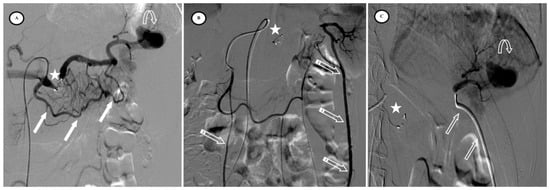

Figure 5.

Secondary arteriovenous (AV) fistula development 30 days after preventive proximal splenic artery embolization (PPSAE). (A) shows PPSAE using Penumbra occlusion device (star), the subsequent development of collateral circulation mainly through the dorsal pancreatic artery and the great pancreatic artery (blank arrows), and the secondary AV fistula (arrow). (B) illustrates the distal microcatheter selection (striped arrow) through radial access. (C) shows microcoil embolization (blank star) with satisfying angiographic results.